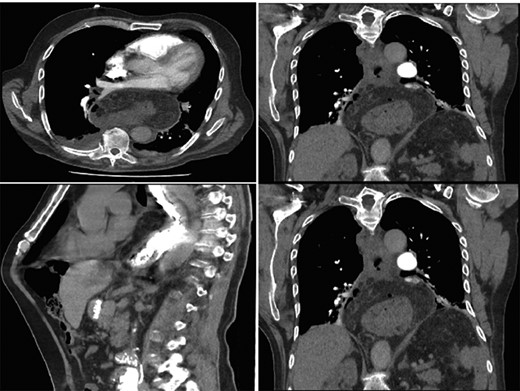

Interval gastroscopy in 2 weeks showed healing mucosal ischemia with slough from 27–30 cm (Fig. 3). Clear fluids were commenced and gradually upgraded to normal diet. Follow-up CT showed no contrast extravasation within posterior mediastinum (Fig. 4) and gastroscopy in 8 weeks showed healed esophagus.

CT scan at 2 weeks showing no contrast extravasation in posterior mediastinum.